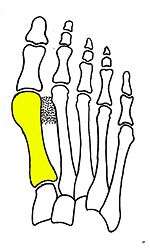

Surgical principle and technique of the syndesmosis procedure

Syndesmosis procedure addresses specifically the two fundamental problems of metatarsus primus varus deformity that gives rise to the bunion deformity. They are leaning and instability of the first metatarsal bone . Syndesmosis procedure uprights the leaning first metatarsal bone with strong binding sutures between it and the second metatarsal bone (Fig. 2) and then also stabilizes it uniquely by creating a fibrous connecting bridge between these two bones (Fig. 3,4). First metatarsal bone can be readily realigned is because by definition of the metatarsus primus varus deformity its first metatarsal is abnormally loose and mobile.